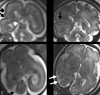

Fig 6.

Same case as Fig 5. A and B, Two coronal T2-weighted single-shot, fast spin-echo sections from studies in gestational weeks 23 and 32, respectively, showing the abnormal value of the right HIA in comparison with the normal contralateral one.